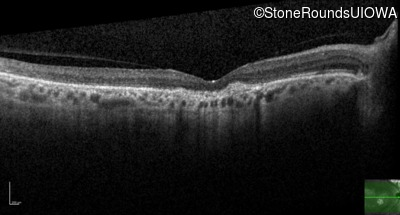

Optical Coherence Tomography - Left - 20/80

Exemplar / OCT Stack

Infrared Fundus Photograph - Right - 20/125 -2